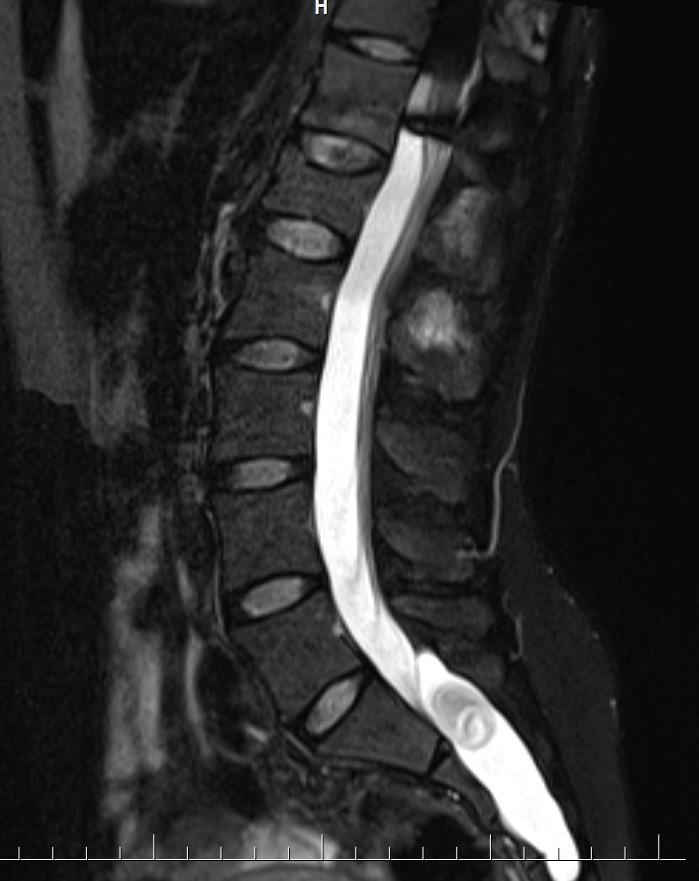

Answer: Occult intrasacralmeningocele

MR images demonstrated large cystic lesion in the sacral canal.

Occult intrasacralmeningoceletypically appear hypodenselesion (isodense to CSF) enlarging the sacral thecal sac which may displace the nerve roots.

MRI is the best modality to assess an occult intrasacralmeningocele.

• T2: hyperintense (isointense to CSF)

• T1C+ (Gd): no enhancement